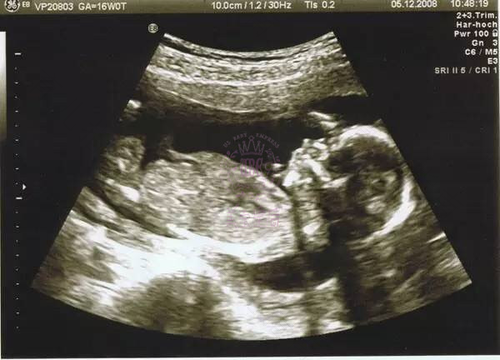

要监测胎儿发育是否正常,除了数胎动外,孕妇可以听胎心,一般情况下怀孕12周就可以听胎心。据悉,胎心正常范围是120到160次/分。另外,监测体重也可以帮助孕妇了解胎儿的发育是否正常,还可以判断自己有没有潜在疾病。一般来说,孕妇在整个孕期平均增加12公斤体重。在怀孕12周内增加1公斤;13周到28周增加5到6公斤;28周以后每月增加500克左。

好奇小提示:准妈妈不要经常自摸宫底来测胎儿的发育,可以听专家意见采取听胎心的方式来测。